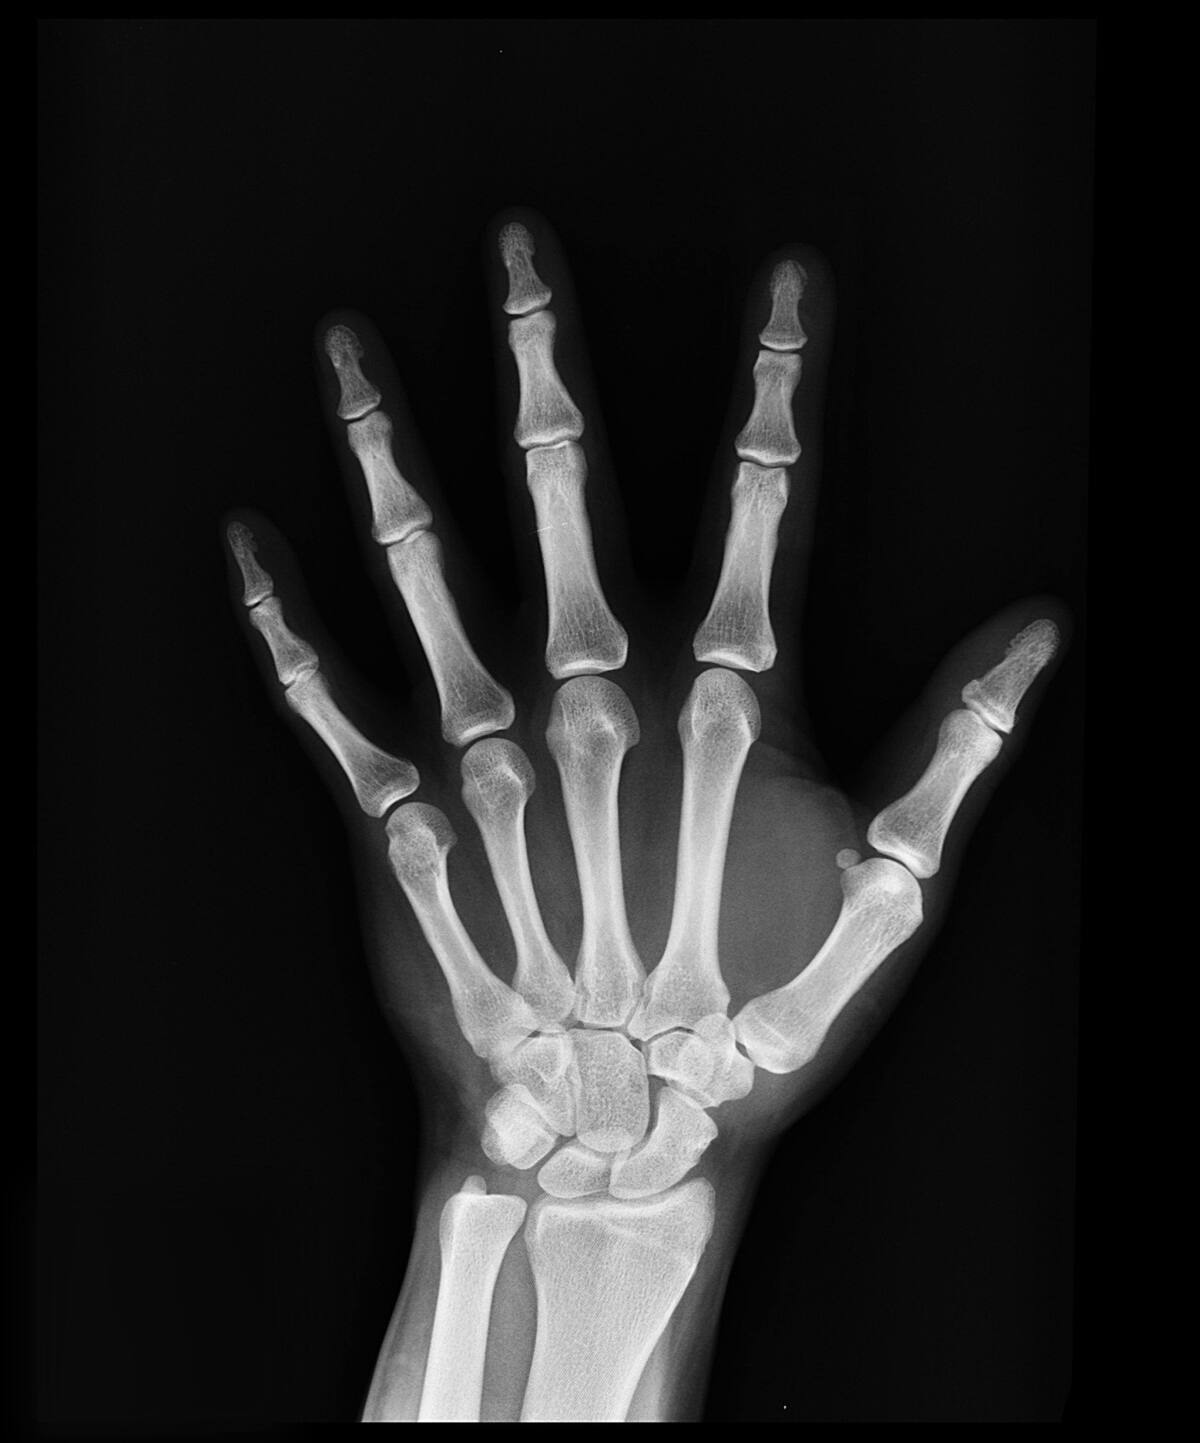

Comer lácteos no es la única forma de fortalecer los huesos. Foto: Pexels.